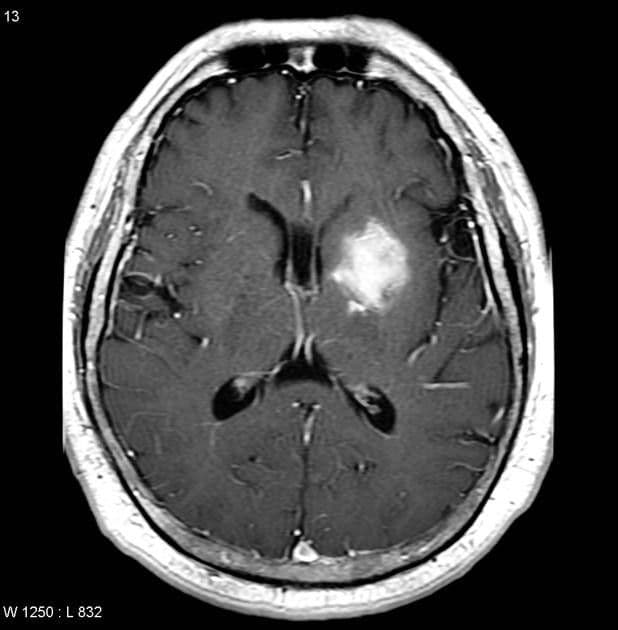

Выставить верный диагноз и получить максимум информации о состоянии больного, можно благодаря инструментальным методам диагностики. Оптимальным вариантом считается проведение КТ головного мозга.

Компьютерная томография позволяет уточнить вид патологии, место ее сосредоточения, понять насколько сильно пострадал головной мозг, затронуты ли желудочки и пр. Главная проблема заключается в том, что выполнить КТ в кратчайшие сроки не всегда возможно. В этом случае врачам приходится ориентироваться на симптомы болезни.